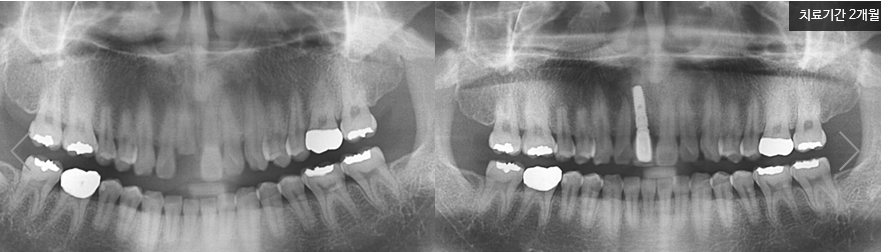

앞니에 남은 뿌리가 없는지 방사선 촬영으로 꼼꼼히 확인한 후 마취한 뒤 정확하게 계산된 위치에 임플란트를 식립합니다. 잇몸뼈가 얇은 부위인 만큼 픽스쳐의 노출을 막기위해 알맞은 양의 뼈이식을 진행합니다.

실제 명동 라임나무치과 앞니임플란트후기 입니다. 가로로 치아가 부러져 치아뿌리를 제외한 치아가 거의 남지 않아 발치가 불가피하셨던 환자분의 케이스인데요

우선 임플란트 뿌리가 노출되지 않도록 잇몸에 단단히 식립한 후 양옆의 치아 모양과 색, 질감을 고려해 최대한 자연치아와 유사하게 보철을 제작하였습니다.